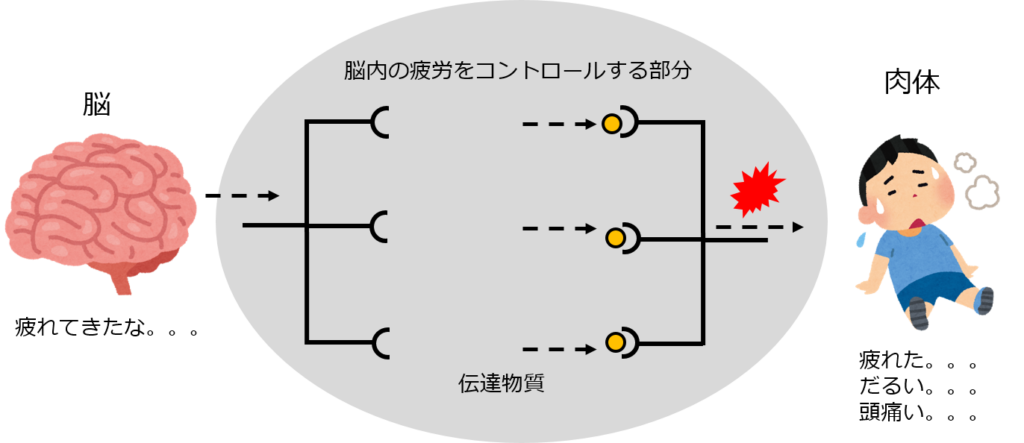

Operation Blue Wind 乱用 中毒 依存ってなに

Operation Blue Wind 乱用 中毒 依存ってなに